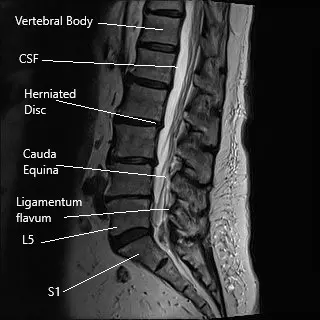

MRI of the lumbar spine in sagittal section.

Microdiscectomy is a minimally invasive spine surgery commonly done for the surgical management of sciatica. Sciatica usually occurs as a result of the prolapse of an intervertebral disc. The intervertebral disc may prolapse as a result of age-related wear and tear or due to trauma as a result of fall or repetitive action.

Sciatica is usually managed with nonsurgical treatment and surgical treatment is only indicated in patients who have had no relief with the non-surgical measures. Microdiscectomy surgery involves a small incision in the lower back. The spine surgeon separates or cuts the muscles and tissues to reach the diseased disc. The herniated disc is then removed and pressure over the spinal nerve is relieved.